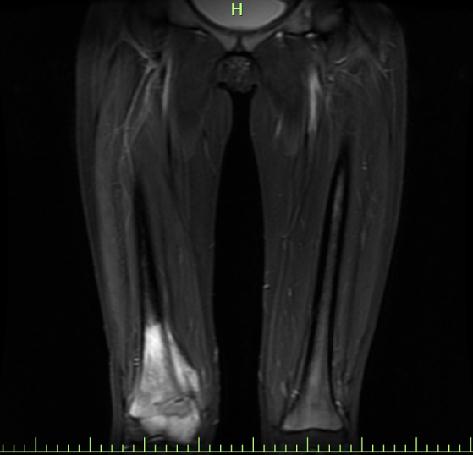

佳佳的父母着急了,赶紧带着她到当地医院就诊。经一系列检查,父母等来了晴天霹雳的结果,佳佳右膝盖上方骨头处被发现有肿块,经穿刺活检后病理诊断为骨肉瘤。

“骨肉瘤虽然发病率不高,但这是青少年身上最常发生的一种恶性肿瘤。根据相关数据,未发生转移的骨肉瘤患者经过规范化治疗后5年生存率为60%-70%,但有约10%-15%的患者在初诊时已存在远处转移,而转移患者5年生存率显著降低,预后不佳。”陈斌主任医师表示,经过进一步检查,还好佳佳右膝盖这里的骨肉瘤并未发生转移。

随后,骨科陈斌主任医师、童翔副主任医师为佳佳进行了手术,完整切除了骨肉瘤及其侵犯的骨质,由于肿瘤长在膝盖上,专家团队为佳佳进行了人工膝关节置换。同时结合佳佳术前影像学数据,专家团队用3D个性化假体打印系统,为佳佳精准地打印了适合的人工假体,从而补全缺损的骨头。

下,骨肉瘤最常发生在四肢,特别是膝关节周围,症状主要为疼痛、肿胀感,在活动后加剧,夜间疼痛加剧,出现肿块,并不断增大。”

骨肉瘤的疼痛多见于关节处,位置比较固定,而且疼痛开始时较轻、间隔疼痛,然后发展得愈来愈严重,晚上痛感更强烈,休息一般对缓解症状没有帮助,止痛药一般也没有用。随着疼痛的加重,局部会逐步出现肿块、发红,且疼痛部位的局部皮肤温度要高于其他地方。